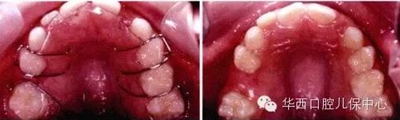

圖示:乳尖牙至乳磨牙的寬度大于繼承恒牙的寬度

剩余的間隙稱為替牙間隙(leeway space)

圖為幾種活動擴(kuò)弓矯治器的設(shè)計